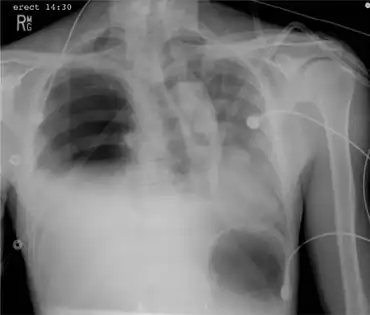

| Portable chest x-ray demonstrating a right-sided tension hemopneumothorax | |

Hemopneumothorax, or haemopneumothorax, is the condition of having air in the chest cavity (pneumothorax) and blood in the chest cavity (hemothorax). A hemothorax, pneumothorax, or the combination of both can occur due to an injury to the lung or chest.[1]